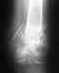

Закрытый спиральный перелом нижней трети обеих костей правой голени со смещением |

Добрый день! 28.01.2016 Был мной был получен данный диагноз по средствам катания с горок на лыжной базе. В этот же день в больнице просверлили пятку вставили спицу и положили на вытяжку. 2.02.2016 Была произведена операция и был установлен аппарат илизарова (т.К. Врачи сказали что перелом сложный и будет лучше с аппаратом чем с пластиной). 29.02.2016 Сделали рентген (снимок прилагается), снимок сделан как я понял с целью убрать самую первую спицу которая была сделана для вытяжки и которая фиксирует в одном положении. Собираюсь с этим снимком теперь к врачу. Но судя по снимку что то ничего не изменилось или так и должно быть ? Ногой потихоньку двигаю лежа(поднимаю, сгибаю) ну и на костылях немножко прыгаю. Подскажите пожалуйста есть ли какие либо улучшения или наоборот ? А то что то тревожно стало когда сегодня снимок посмотрел а там на мой взгляд все без изменений. Заранее благодарен.